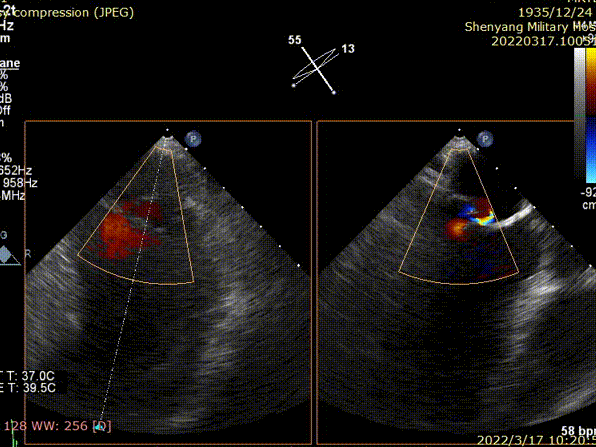

术前TEE显示二尖瓣重度反流,反流位置位于A2/P2区